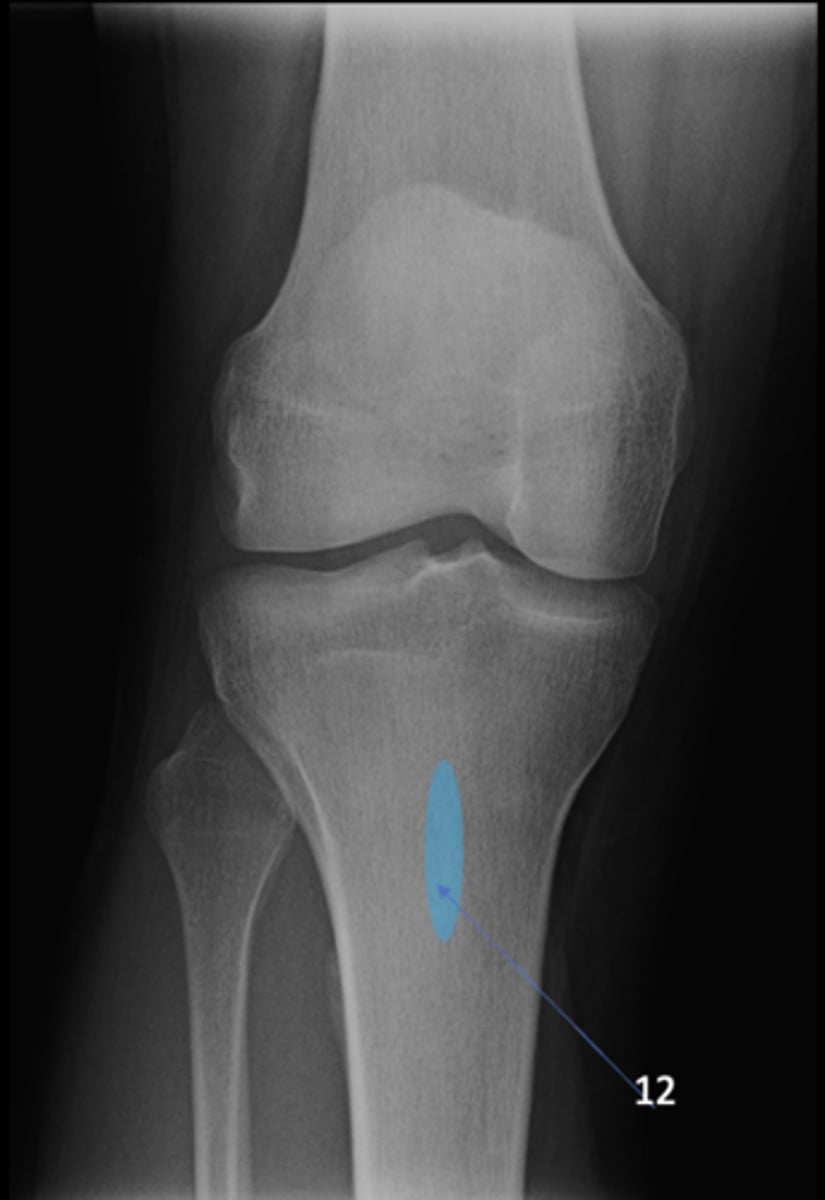

8

New cards

Left ischial spine

ID 8

<p>ID 8</p>

9

Right fovea capitis

ID 9